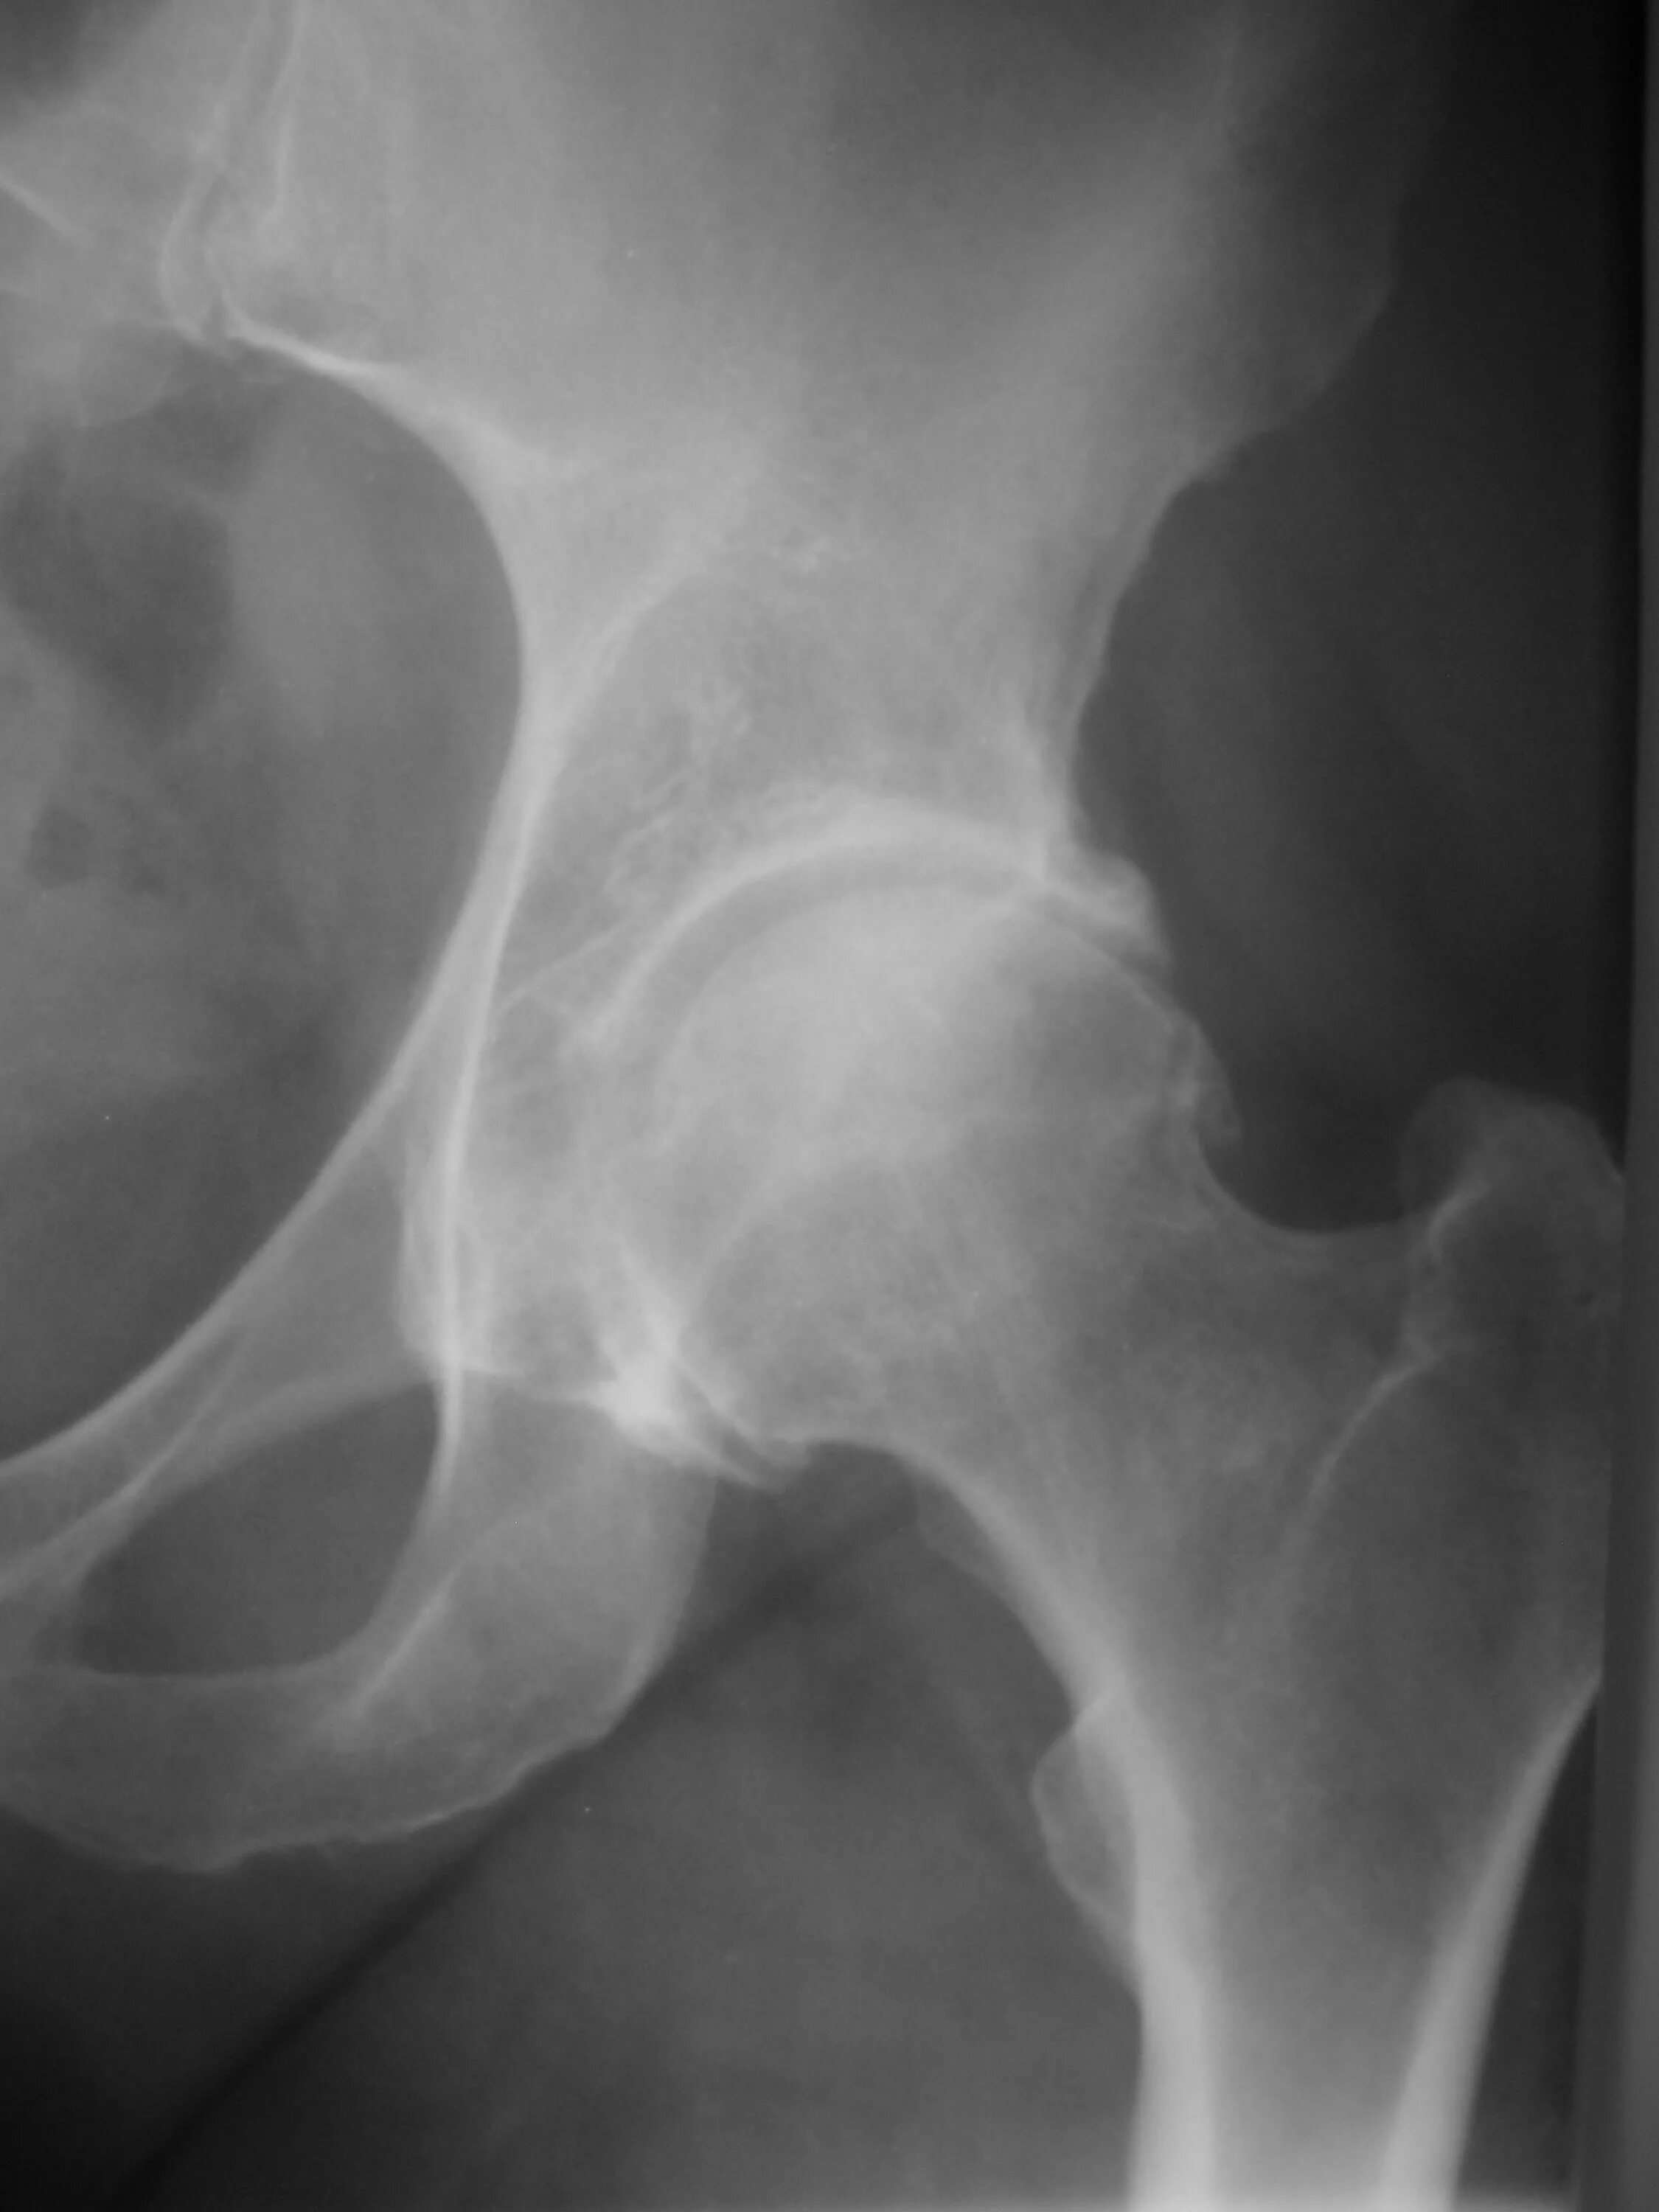

Склероз вертлужной впадины